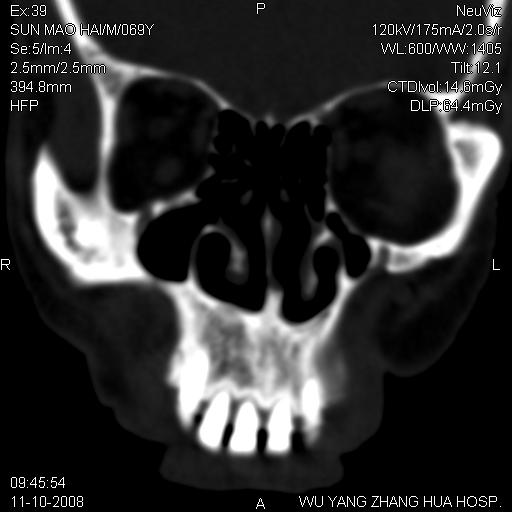

标题: CT16568:右面部瘘管半年余,无其它不适. [打印本页]

标题: CT16568:右面部瘘管半年余,无其它不适.

考虑右上颌异位齿(或斜向阻生齿)并根尖脓肿。

右上颌异位齿(或斜向阻生齿)

1.右上颌异位齿

2.右上颌化脓性骨髓炎

3.右下鼻甲肥大

支持三楼意见。(这种长法还真少见,再长再尖点就成獠牙了。)